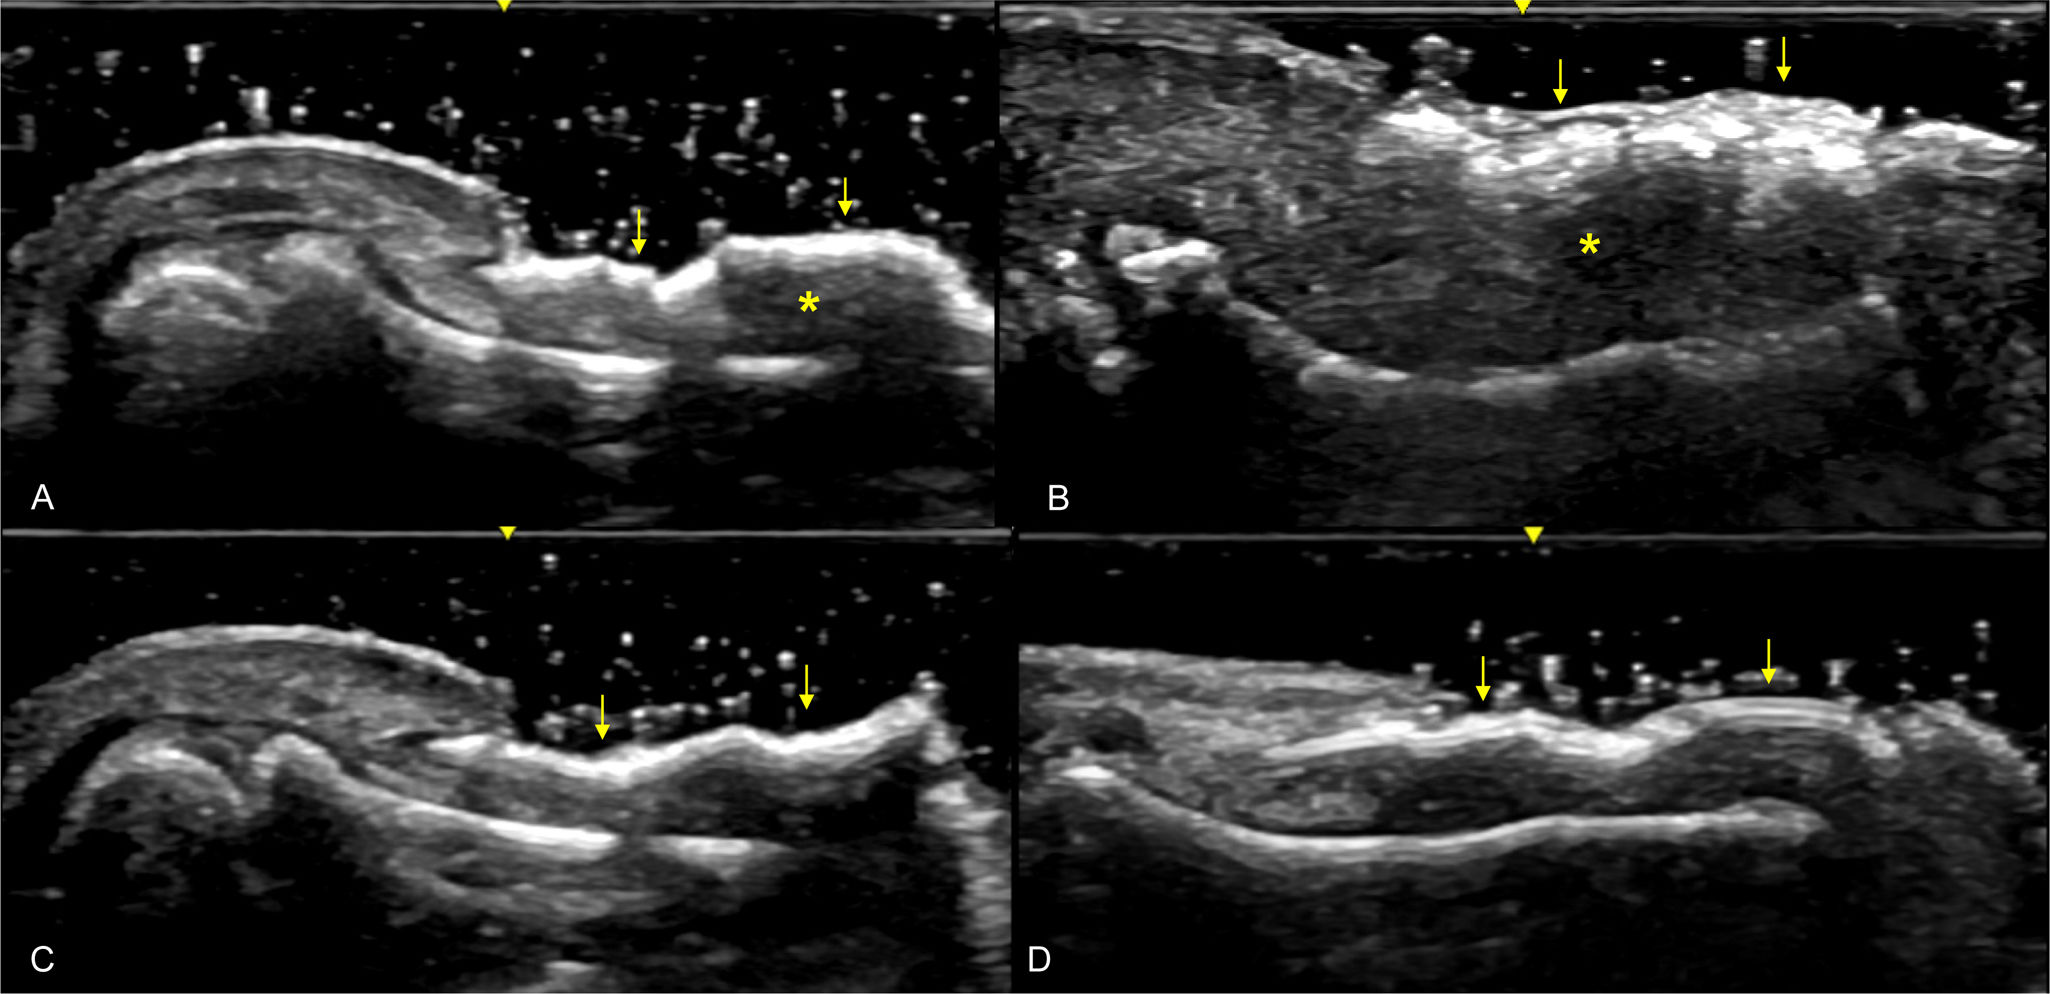

Ultrasound is especially useful for detecting early psoriatic nail changes, such as minimal thickening of the nail bed or slight loosening of the ventral plate (Fig. 6). As the disease progresses, more pronounced alterations occur, including thickening of both the ventral and dorsal nail plates. In these advanced stages, the trilaminar structure of the nail plate, characteristic of healthy nails, is completely lost. The nail plate becomes thickened, wavy, and hyperechoic, with an inhomogeneous appearance [133,137] (Fig. 7). Power Doppler (PD) is particularly valuable for assessing inflammation in the nail matrix and bed, grading vascularization on a scale from 0 to 3, where higher values indicate greater inflammation [20].

Fig. 7.(A–D) Late Psoriatic Nail Changes (Longitudinal view). Sonographic image obtained using Logiq e US system with an 8–18i MHz linear transducer. Grayscale ultrasound reveals pronounced thickening of both the ventral and dorsal nail plates, resulting in the complete loss of the normal trilaminar structure characteristic of healthy nails. The nail plate appears as a single hyperechoic layer with inhomogeneous thickness (arrow), while the nail bed is significantly thickened (asterisk). In these advanced stages, the nail plate becomes thickened, wavy, and hyperechoic, exhibiting an overall inhomogeneous appearance.